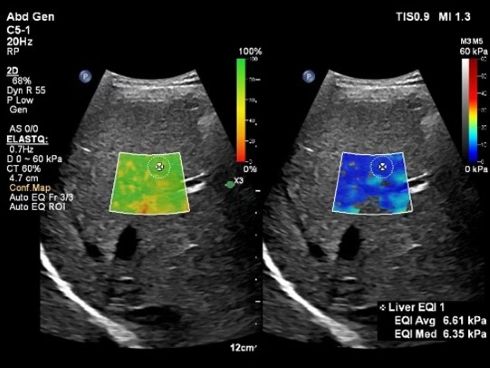

「ElastQ」は、非侵襲的に組織の硬さを評価する技術「Share Wave Elastography」を用いて肝臓の硬さを計測するアプリケーションだ。新たに追加した自動化機能は、計測に適したフレームやROIポジションを自動で判別し、計測結果を表示する。この機能により、検査時間が最大60%短縮し、99%の再現性が示された。

キャプション 「Auto ElastQ」による肝硬度の自動計測 出所:フィリップス・ジャパン